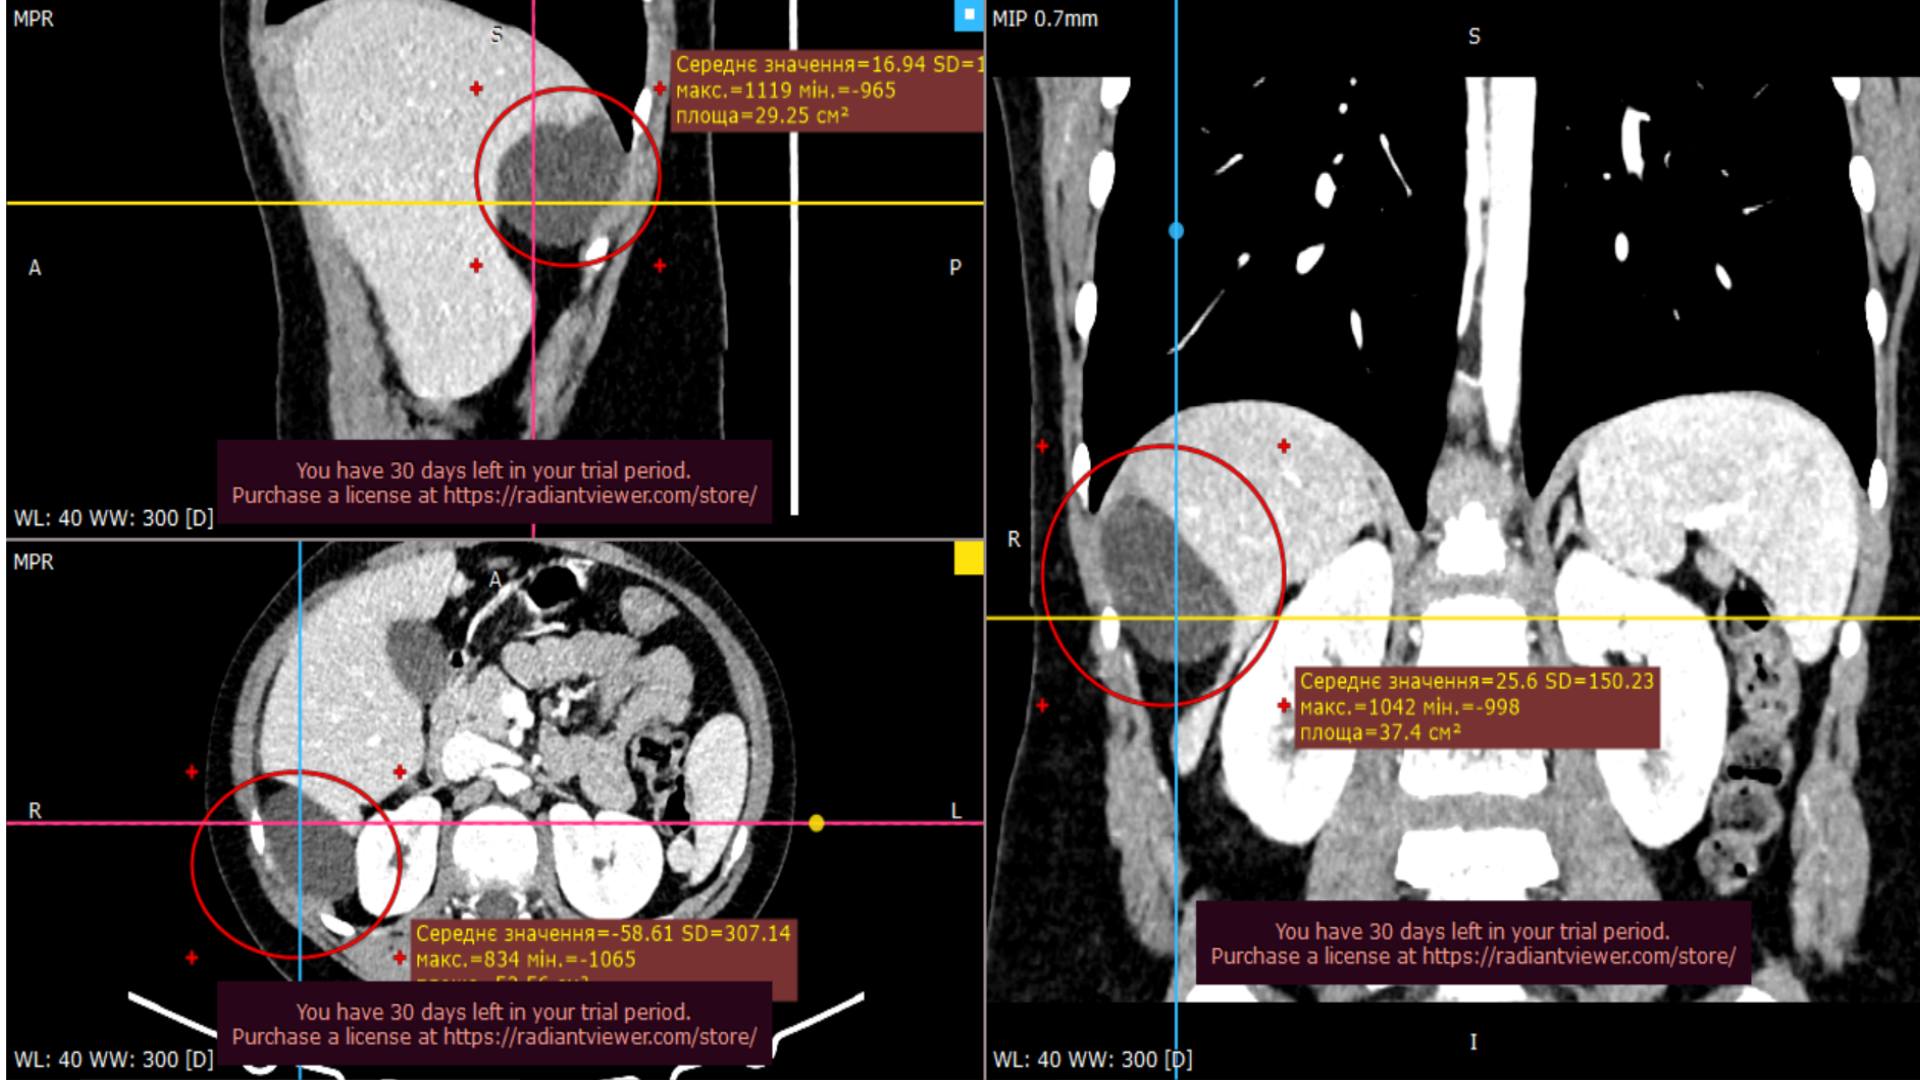

Лікарі виконали хірургічне втручання лапароскопічно – малоінвазивною методикою через невеликі розрізи. Однак операція була складною через локалізацію кісти: навіть за знімками комп’ютерної томографії неможливо було точно визначити, чи цей великий утвір походить із печінки, чи він розташований в черевній порожнині. Загалом операція тривала чотири години.